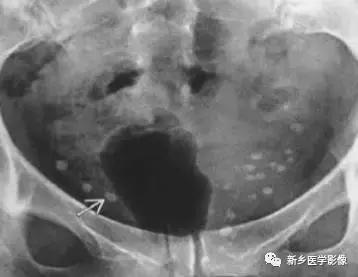

子宫平滑肌瘤(纤维瘤)

主要位于盆腔内,表现为不均一的点状钙化